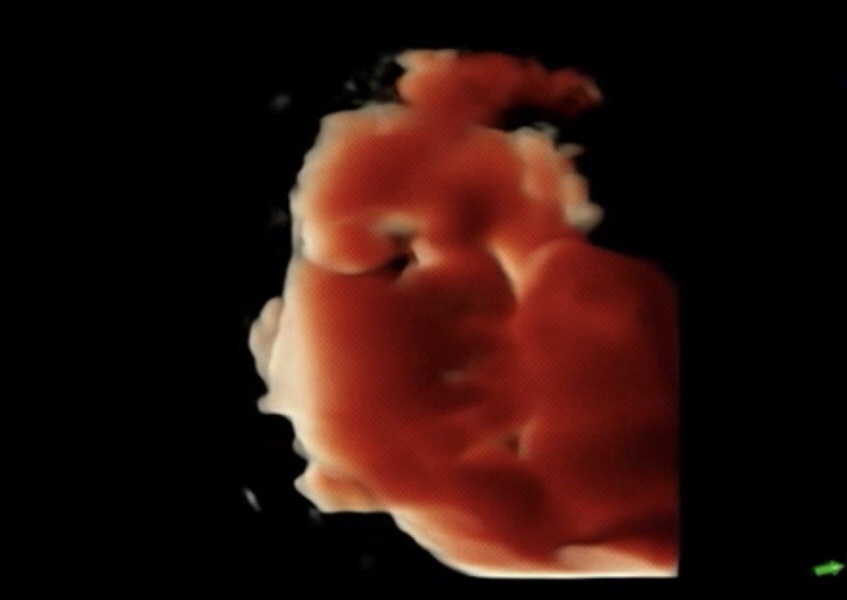

そして エコー 。

今日は 今までで1番

お顔を キレイに見せてくれた ❤︎

ちょっと分かりにくいやつを 。

お口をニッてしたり

モグモグしたり

もうめっちゃ可愛くて

帰ってからも 何度もみてるよ ☺️

癒される 。❤︎